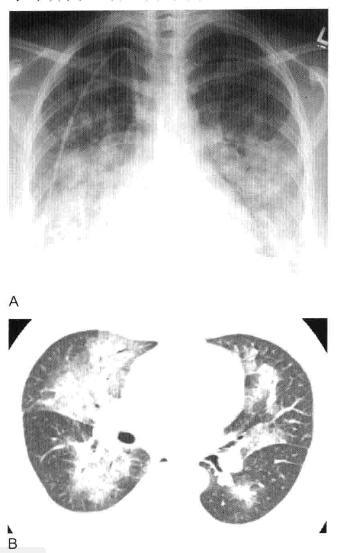

图1 实变:均匀致密影、纹理遮盖,空气支气管征和CT血管造影征

A. 肺水肿所致的右肺实变。可见双侧实变肺内 空气支气管征,肺血管模糊;B.右肺中下叶肺炎患者增强CT显示病变区均匀实变、肺体积保持不变,空气支气管征(黑色箭头)和致密学观影(白色箭头),其密度高于邻近实变肺组织(即“CT血管造影”征)